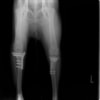

術前正面像

術前のTPAは左後肢33.1°右後肢26.8°でしたがTPLO実施により左後肢5.5°右後肢12°に矯正されました。